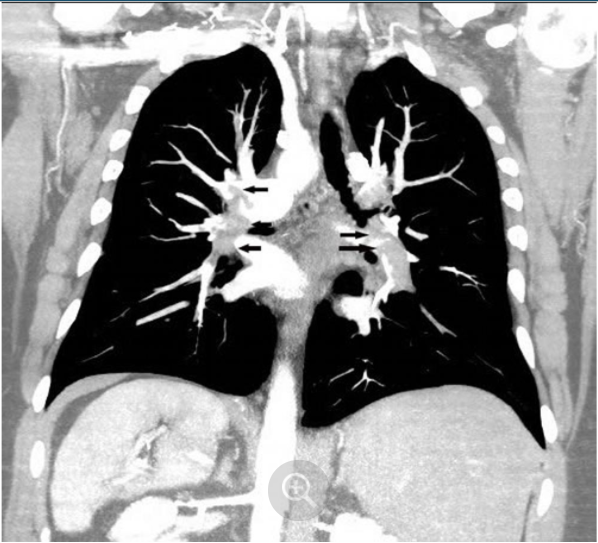

冠状重建CT肺动脉造影